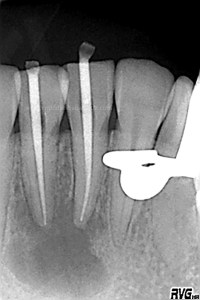

En una segunda sesión, obturamos los conductos tridimensionalmente, conductos acintados. Usaríamos la técnica de Ola continua de Buchanan haciendo un backfilling con la Pistola ObturaII:

Debido al estudio anteriormente citado, se empezó a hacer el tratamiento de ortodoncia una vez que se comenzó a ver una evolución positiva, con signos claros de regeneración a los 6 meses .

(revisión a los 6 meses)